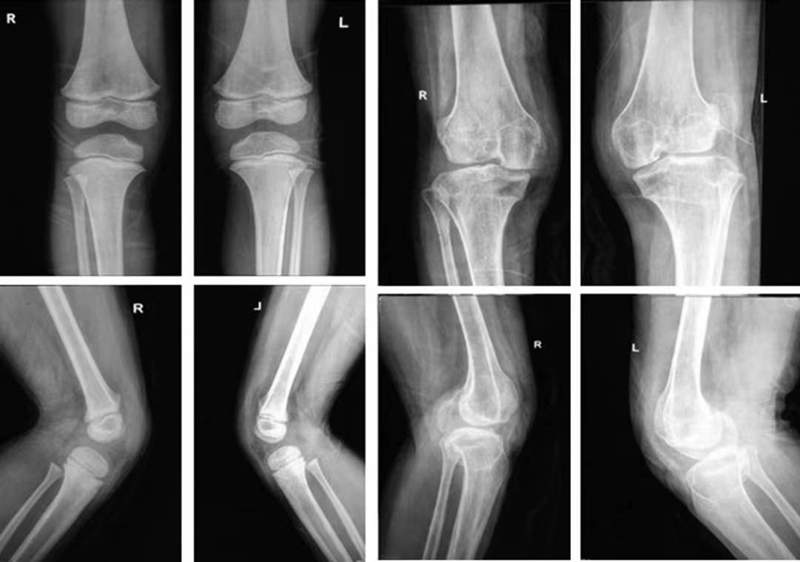

正常髌骨中心点应位于下肢轴线上或稍内侧(图1)。对于髌骨不稳定,膝关节正位像可见髌骨偏离正常的位置,向外侧移位(图2、图3)。

图2 膝关节正位X线成像显示了双侧髌骨偏离正常的解剖位置,明显向外侧移位